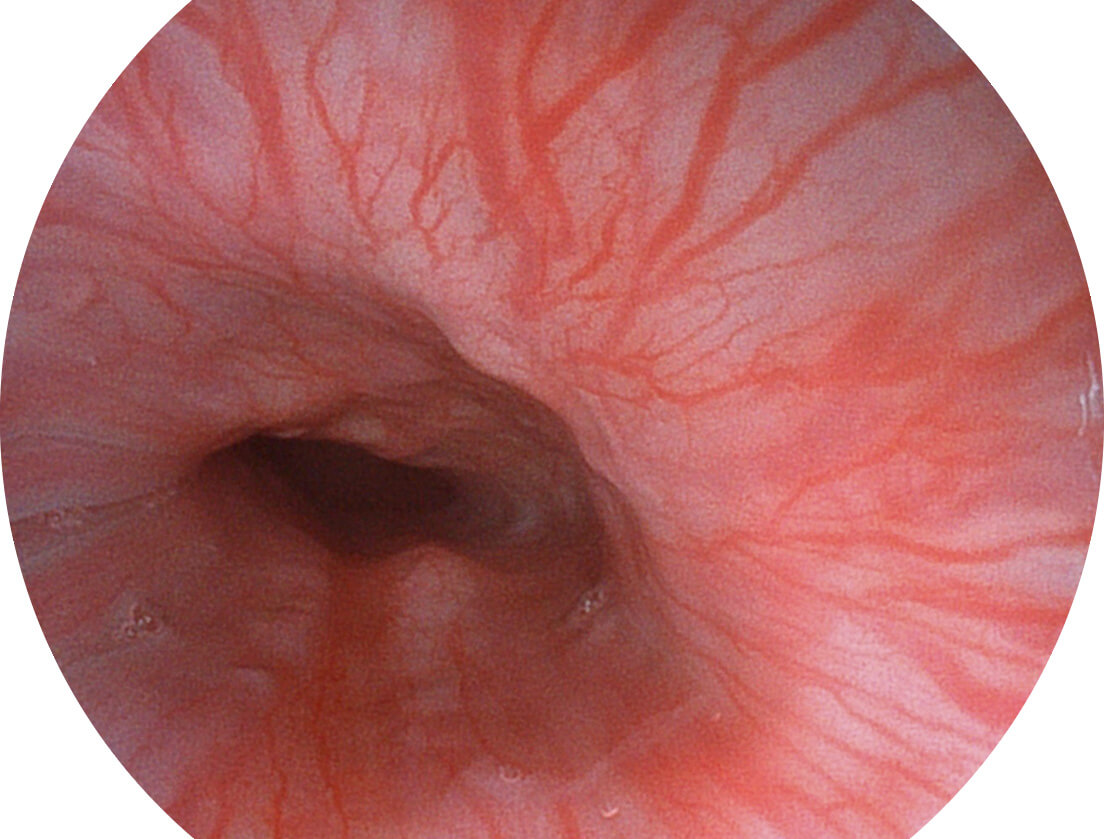

白光图像

SFI图像

采用光路合束技术,光谱自由度高,实现了更丰富的照明模式,染色模式SFI及VIST,从远景到近景,助力消化道早期疾病诊断。